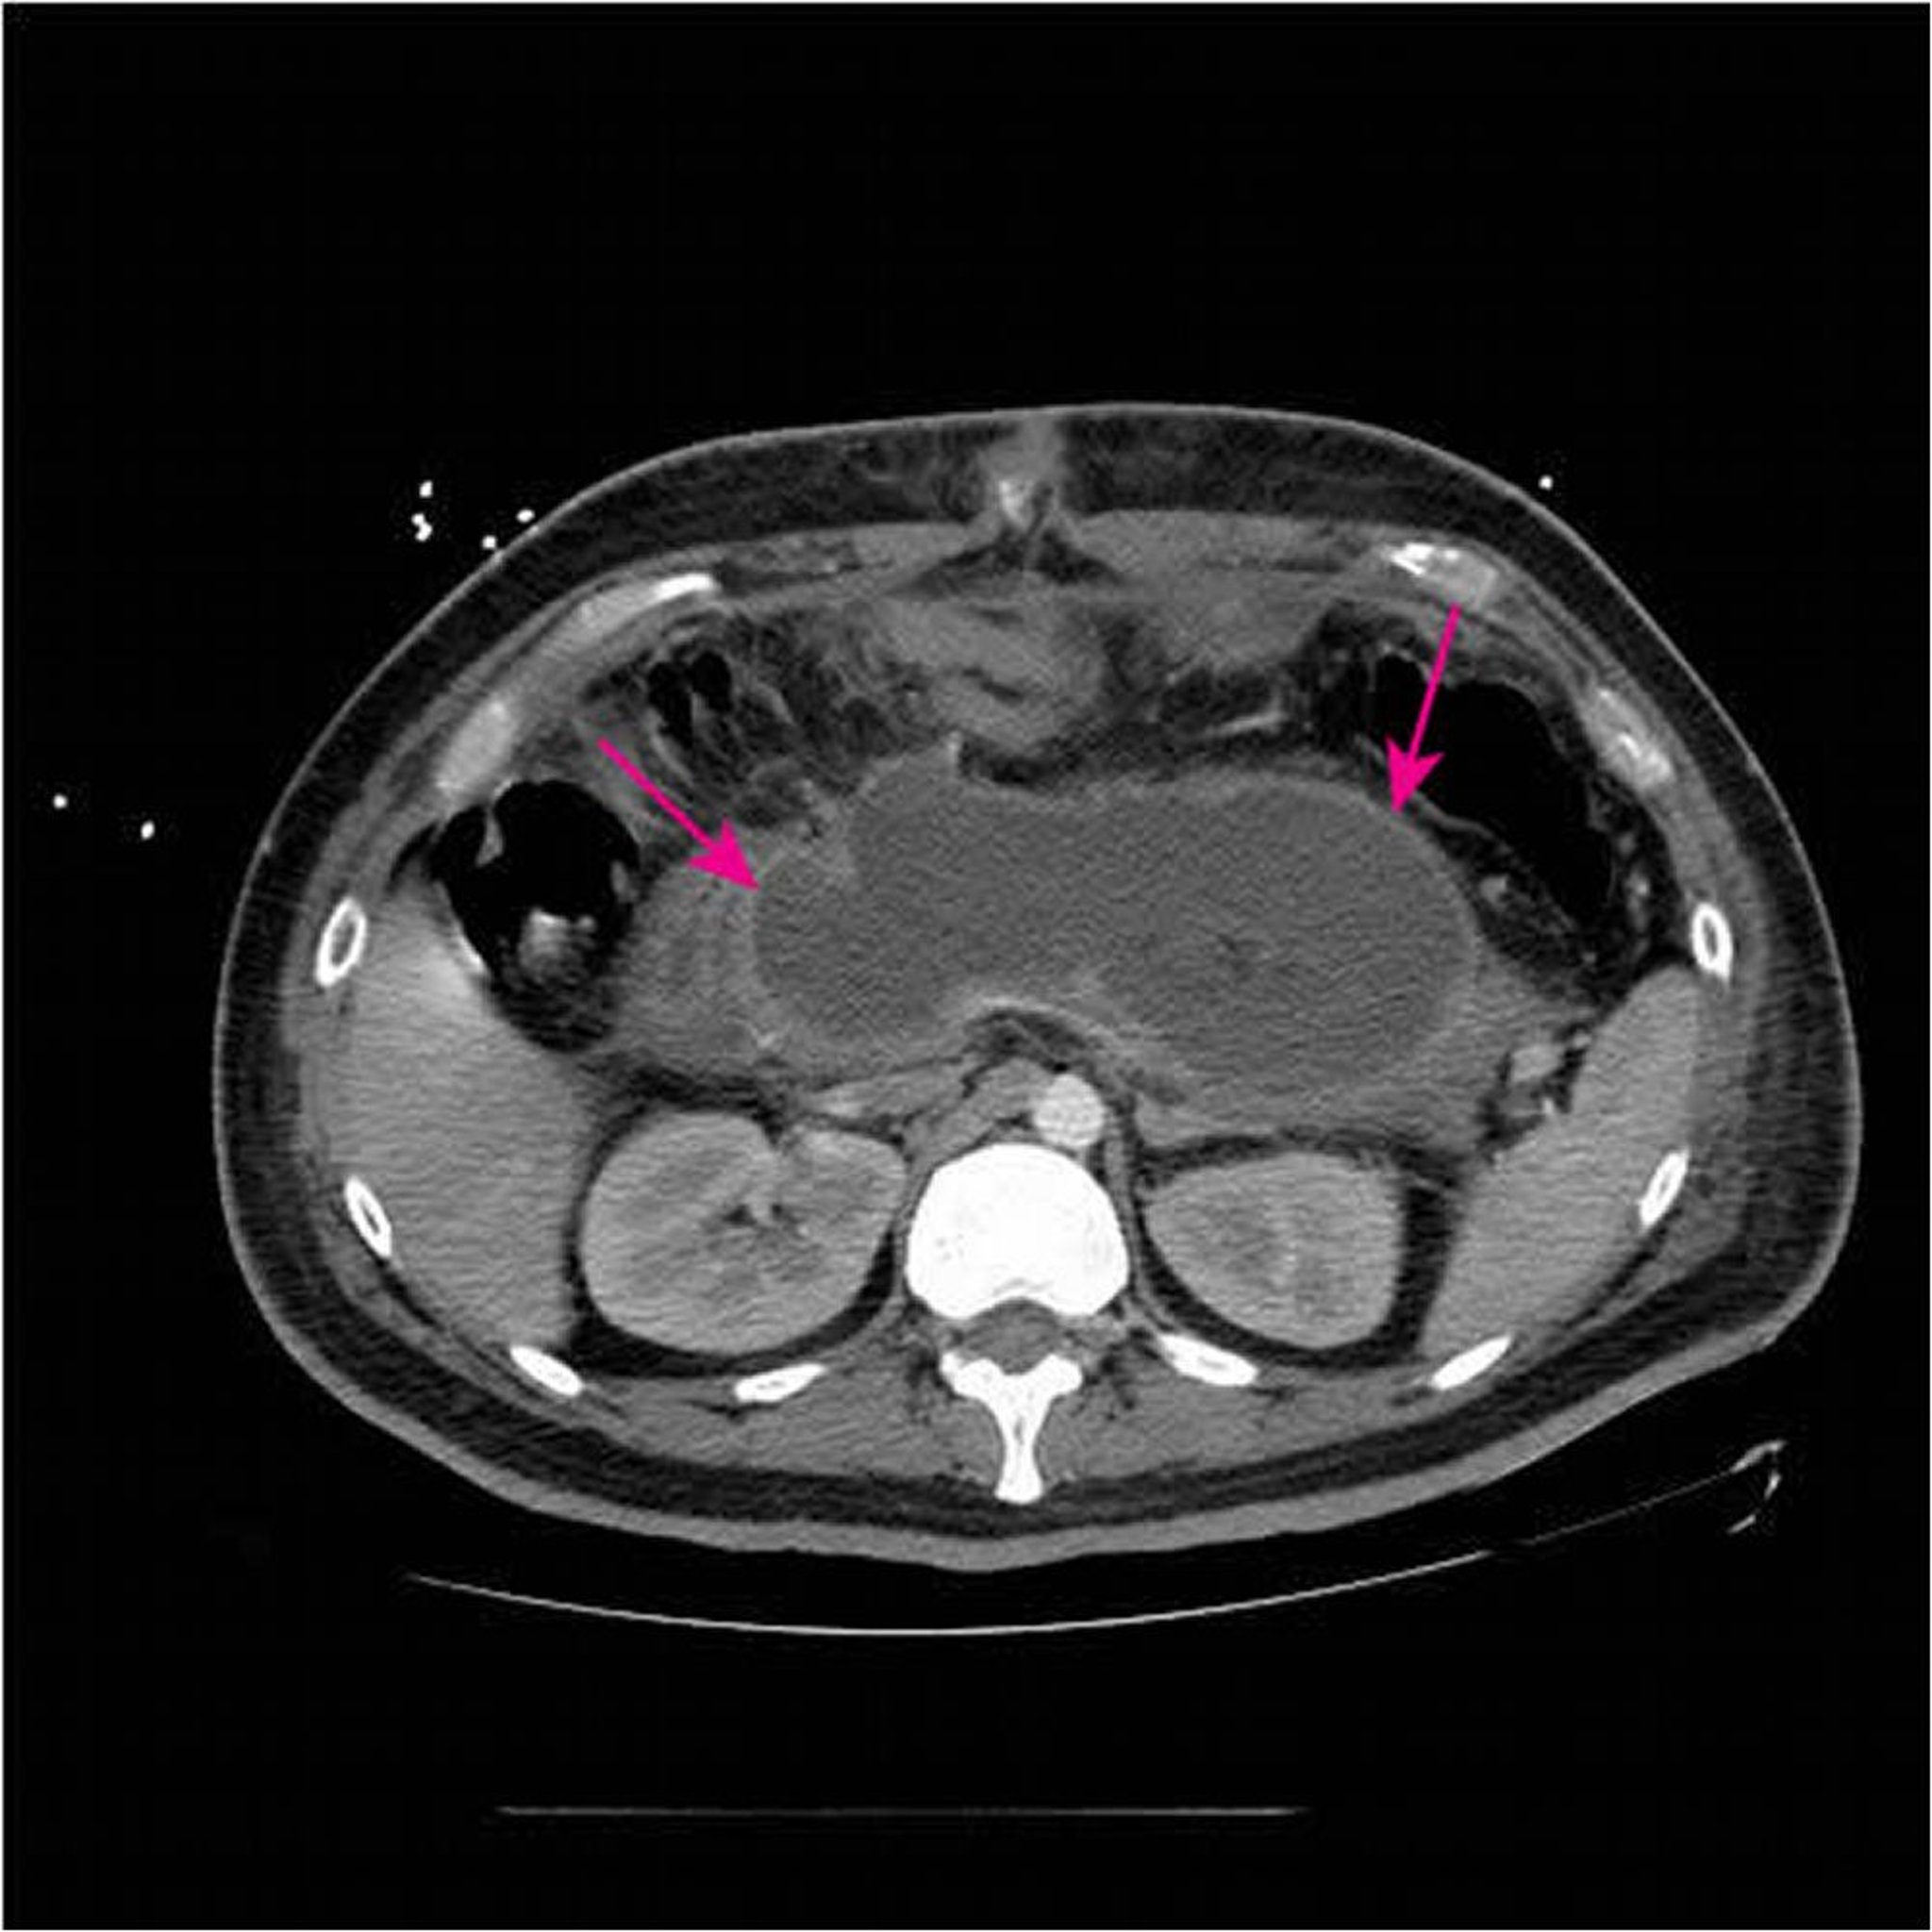

Эта КТ с внутривенным и оральным введением контрастного вещества показывает крупное острое некротическое скопление (стрелки), замещающее большую часть ткани поджелудочной железы в период времени < 4-х недель от первоначального обнаружения некротизирующего панкреатита.

Image courtesy of Sonam Rosberger, MD.